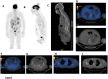

The International Myeloma Working Group (IMWG)recommends FDG PET/CT (Fluoro-Deoxy-glucose Positron Emission Tomography/Computed Tomography) as the gold standard imaging modality for initial evaluation and response to therapy assessment in multiple myeloma. In fact, FDG PET/CT, provides multiple useful indexes to risk-stratify patients and has significant prognostic value. However, multiple myeloma remains a complex disease to interpret on imaging. The Italian myeloma criteria for PET use (IMPeTUs) were proposed to standardize FDG PET/CT reading in multiple myeloma. In this communication an overview on IMPeTUs is provided as well as some examples of application.